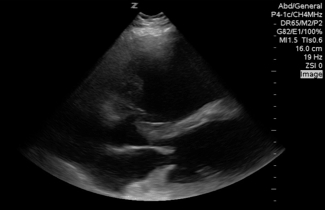

Needs more depth and change the mode to cardiac, but that is a huge RV in the parasternal Long view with an apparent akinetic Apex consistent with tokotsubo vs Acute coronary syndrome less likely acutely elevated right-sided heart pressures seen here with septal bowing right into the mitral valve.

QA of the Day: Huge RV in PSL view with septal bowing takotsubo #pocus #foamus